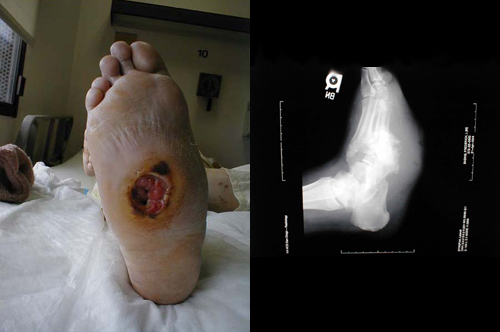

قرحة الاعتلال العصبي

إن الاعتلال العصبي المحدث بسبب داء سكري شديد الوطأة قد أدى إلى حدوث تشوه قدم شاركوت . هذا الأخير أدى إلى إحداث قرحة كبيرة و غير مؤلمة في أسفل القدم . الأشعة السينية تظهر وذمة في النسيج الرخو واضحة المعالم ، كذلك التهدم العظمي المسبب بالتهاب النقي و العظم المستبطن .